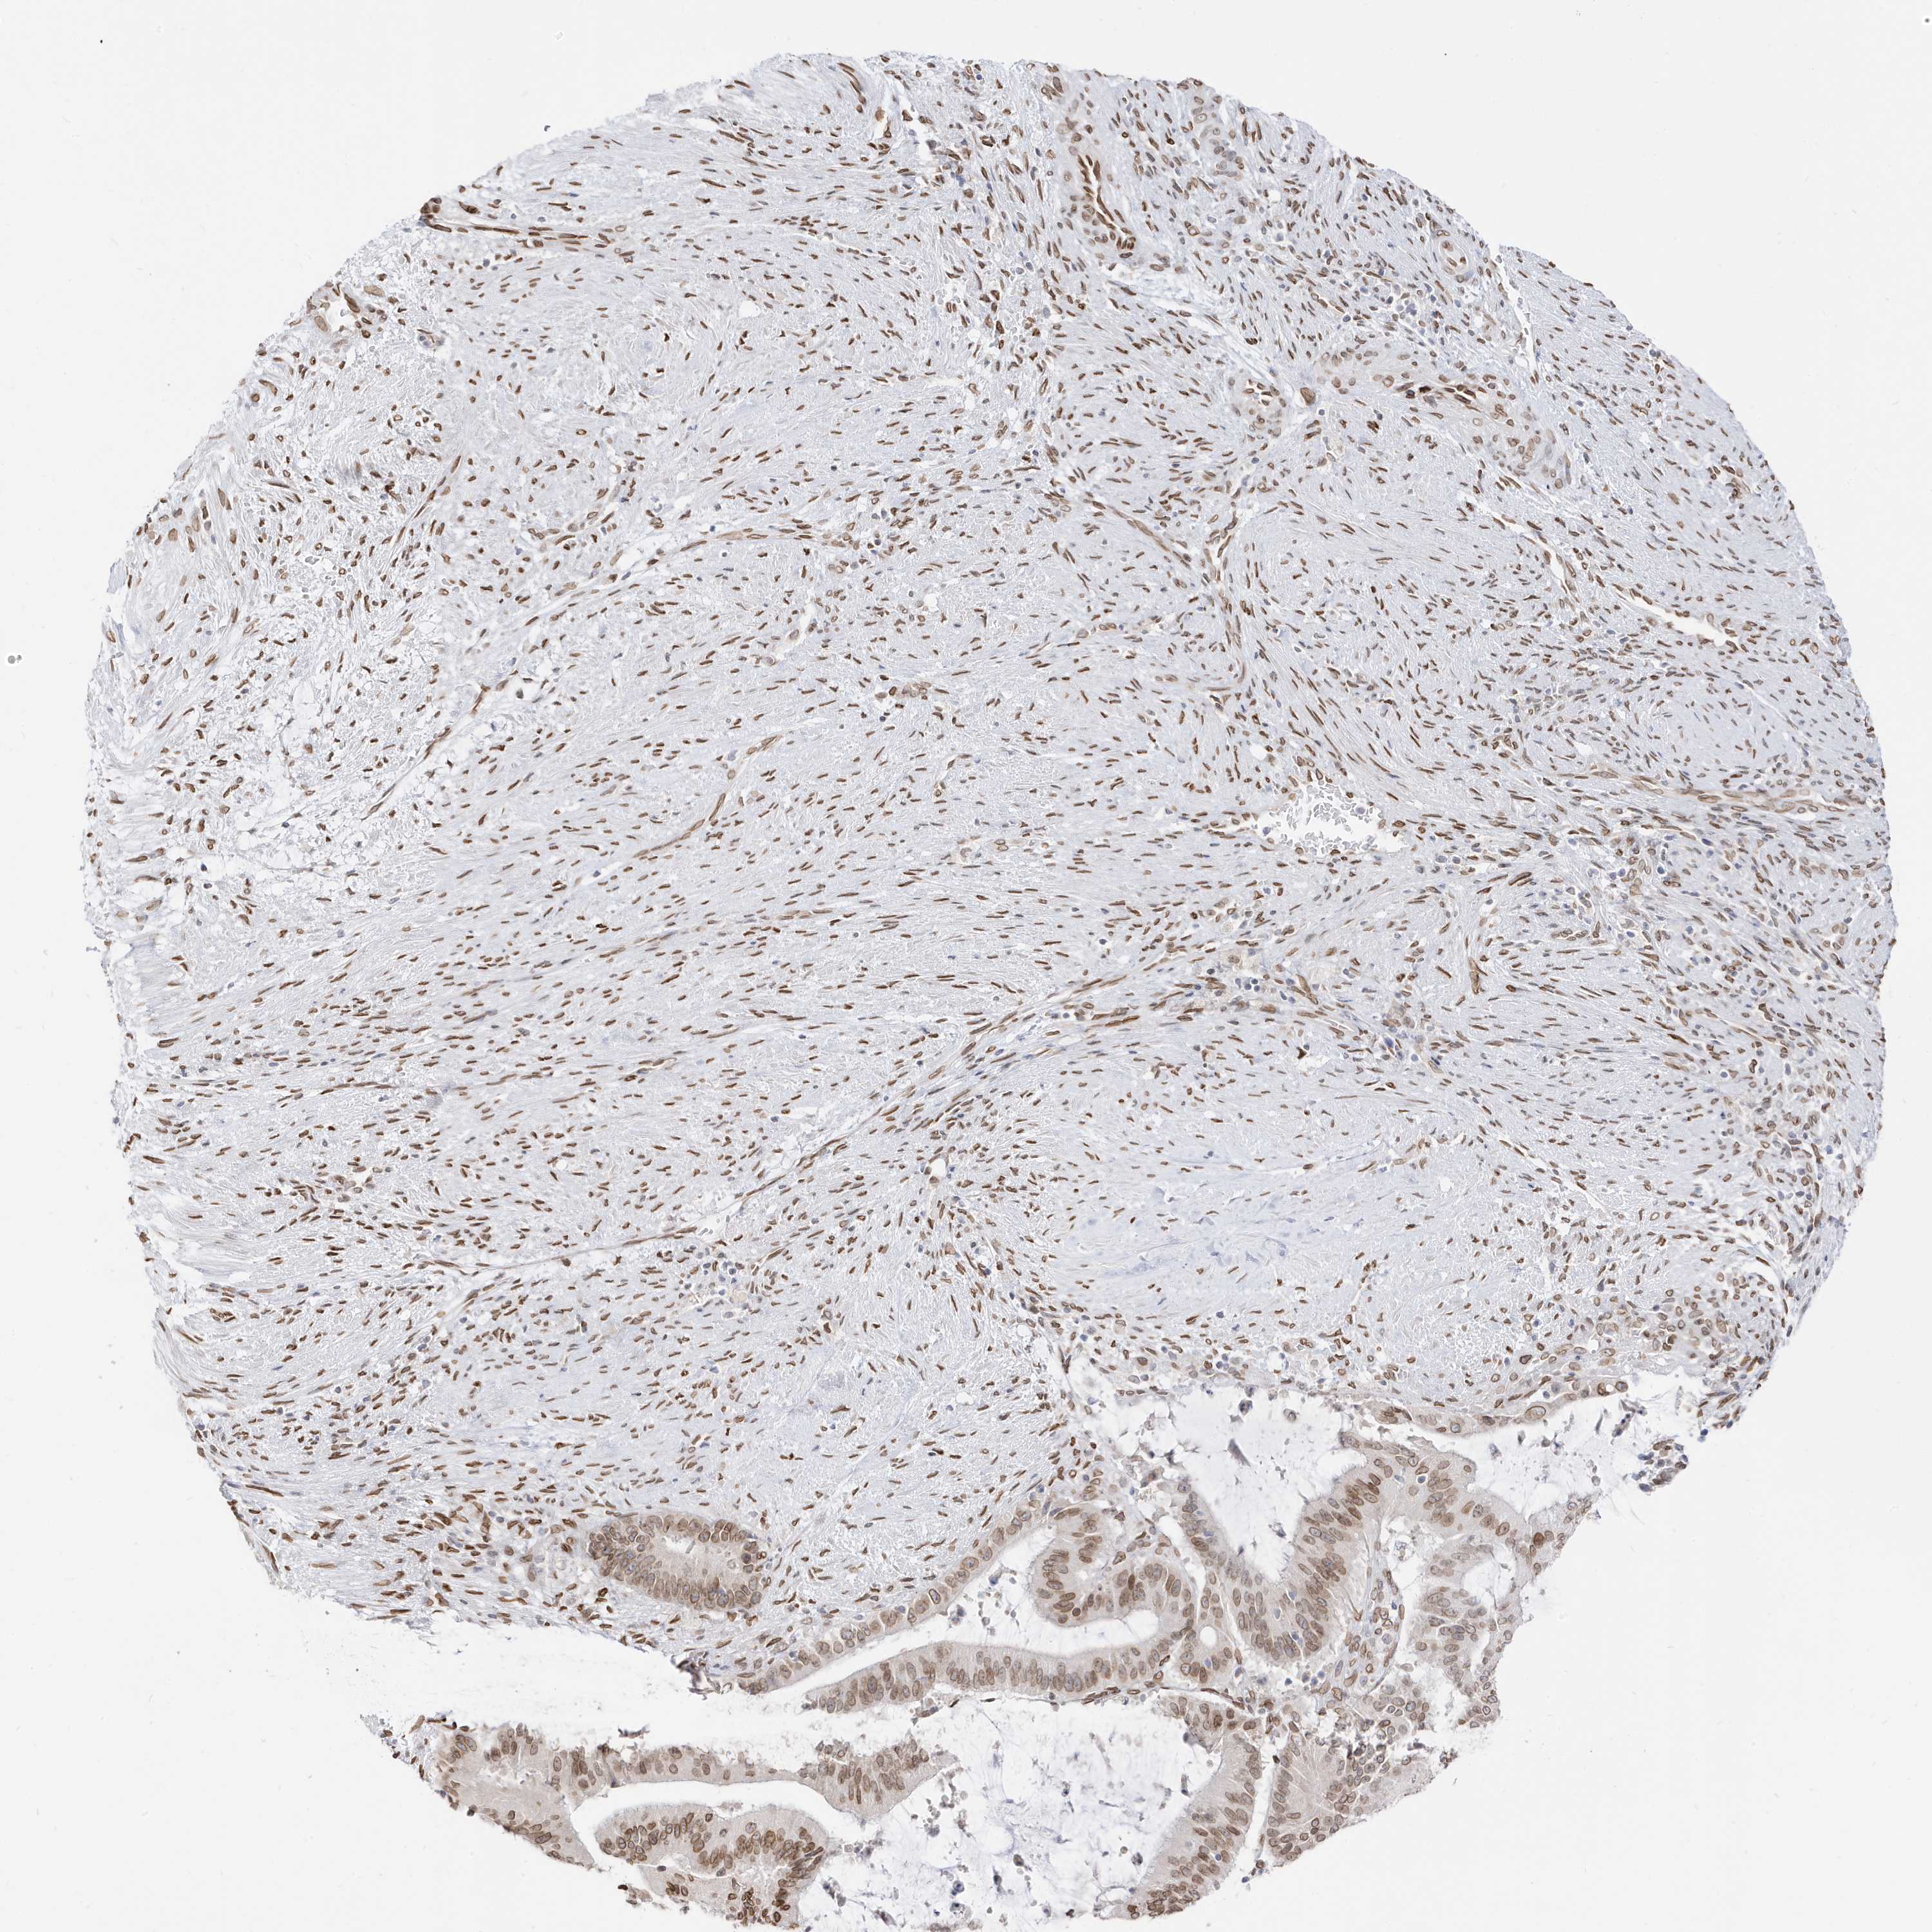

LIVER CANCER - Protein expressioni

A mouse-over function shows sample information and annotation data. Click on an image to view it in a full screen mode. Samples can be filtered based on level of antibody staining by selecting one or several of the following categories: high, medium, low and not detected. The assay and annotation is described here.

Note that samples used for immunohistochemistry by the Human Protein Atlas do not correspond to samples in the TCGA dataset.

Antibody stainingi

Antibody staining in the annotated cell types in the current human tissue is reported as not detected, low, medium, or high, based on conventional immunohistochemistry profiling in selected tissues. This score is based on the combination of the staining intensity and fraction of stained cells.

Each image is clickable and will lead to virtual microscopy that enables deeper exploration of all samples and also displays staining intensity scores, fraction scores and subcellular localization as well as patient and tissue information for each sample.

Antibody HPA029090

Staining

High

Medium

Low

Not detected

Intensity

Strong

Moderate

Weak

Negative

Quantity

>75%

75%-25%

<25%

None

Location

Nuclear

Cytoplasmic/membranous

Cytoplasmic/membranous,nuclear

Cholangiocarcinoma

Carcinoma, Hepatocellular, NOS